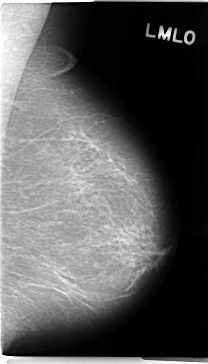

C_0156_1.LEFT_MLO

LEFT_MLO LINES 4728 PIXELS_PER_LINE 2696 BITS_PER_PIXEL 12 RESOLUTION 50 NON_OVERLAY